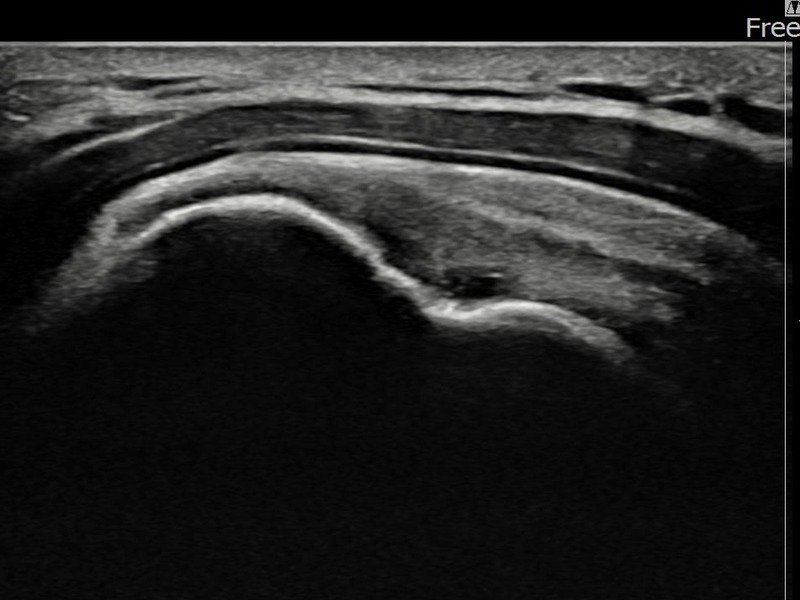

김ㅇㅇ님 · 좌측 극상근건 부착부 광범위 부분파열

좌측 어깨 극상근건 광범위 파열로 수개월간 일상생활이 어렵던 중 내원하셨습니다. 초음파 검사에서 부착부 광범위 부분파열이 확인되었으며, 어깨인대 축소봉합술 시행 후 힘줄 구조가 회복되었습니다.